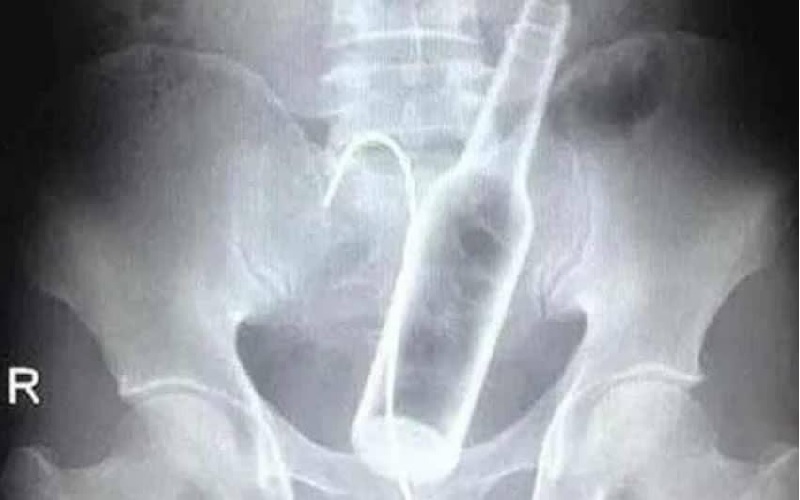

Um homem precisou ser submetido a uma cirurgia na Santa Casa de Poços de Caldas, em Minas Gerais, no último dia 29 de setembro, após dar entrada no hospital com duas garrafas introduzidas no ânus.

Segundo informações divulgadas pela Onda Poços, médicos tentaram remover os objetos — uma garrafa de vidro e outra de plástico — de forma manual, mas o procedimento não teve sucesso. Isso porque uma das garrafas havia se deslocado para uma parte mais alta do intestino, exigindo intervenção cirúrgica.

O paciente passou por uma laparotomia, cirurgia abdominal utilizada para acessar os órgãos internos, e os objetos foram retirados.